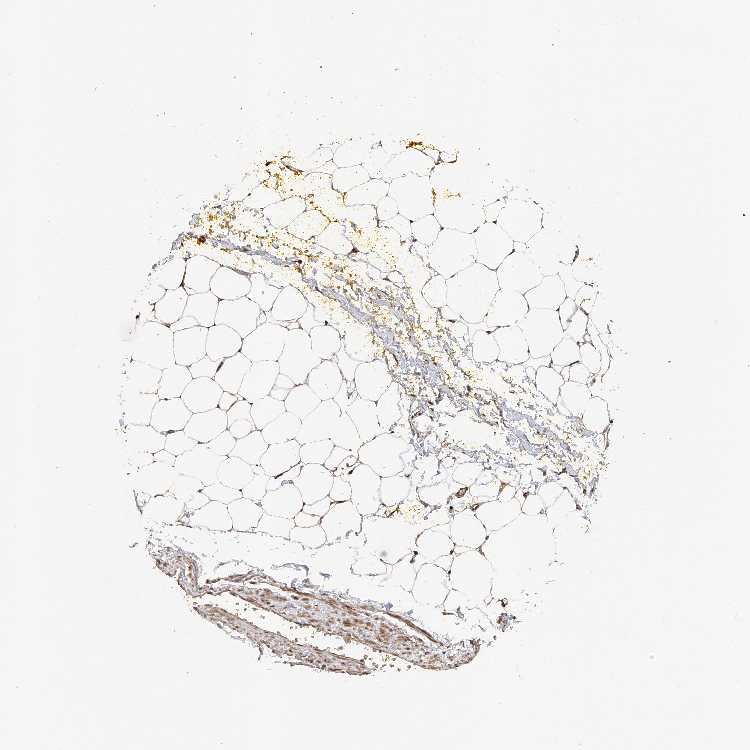

SOFT TISSUE 1 - Antibody stainingi

Antibody staining in the annotated cell types in the current human tissue is reported as not detected, low, medium, or high, based on conventional immunohistochemistry profiling in selected tissues. This score is based on the combination of the staining intensity and fraction of stained cells.

Each image is clickable and will lead to virtual microscopy that enables deeper exploration of all samples and also displays staining intensity scores, fraction scores and subcellular localization as well as patient and tissue information for each sample.

Antibody HPA029152Antibody HPA059824

Chondrocytes MediumNot detected

Fibroblasts MediumNot detected

SOFT TISSUE 2 - Antibody stainingi

Peripheral nerve LowMedium